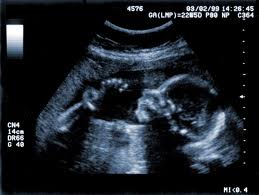

At first the baby didn’t seem aware of the cannula (a straw-shaped instrument attached to the end of the suction tube)…It gently probed the baby’s side…the next movement was the sudden jerk of a tiny foot as the baby started kicking, as if trying to move away from the probing invader. As the cannula pressed in the baby began struggling to turn and twist away. The tiny body violently twisting…being wrung like a dish cloth, twirled and squeezed…then the little body began disappearing…the last thing visible was the tiny, perfectly formed backbone…and then it was gone.